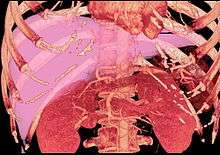

-

Maximum intensity projection (MIP) CT image as viewed anteriorly showing the anomalous hepatic veins coursing on the anterior surface of the liver

Lateral MIP view in the same patient